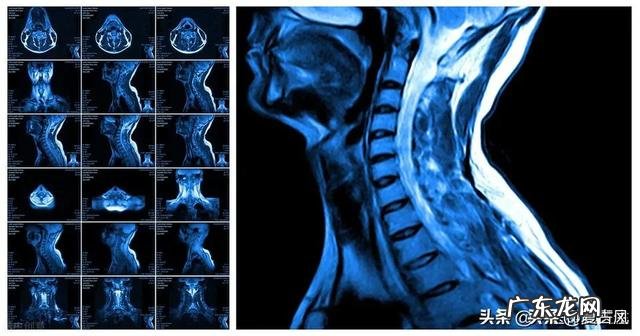

后来,他告诉我说,到目前为止,颈椎病并没有特效药可zhi,一切只能靠平常的保健与调养 。接着他说,”我教你一套自创的颈椎病保健操,你回去后可以试试,一般半个月就见效,若长期坚持下去,完全可以预防颈椎病的发作 。说罢,他就在动车站里现场教我这套颈椎病保健操了 。